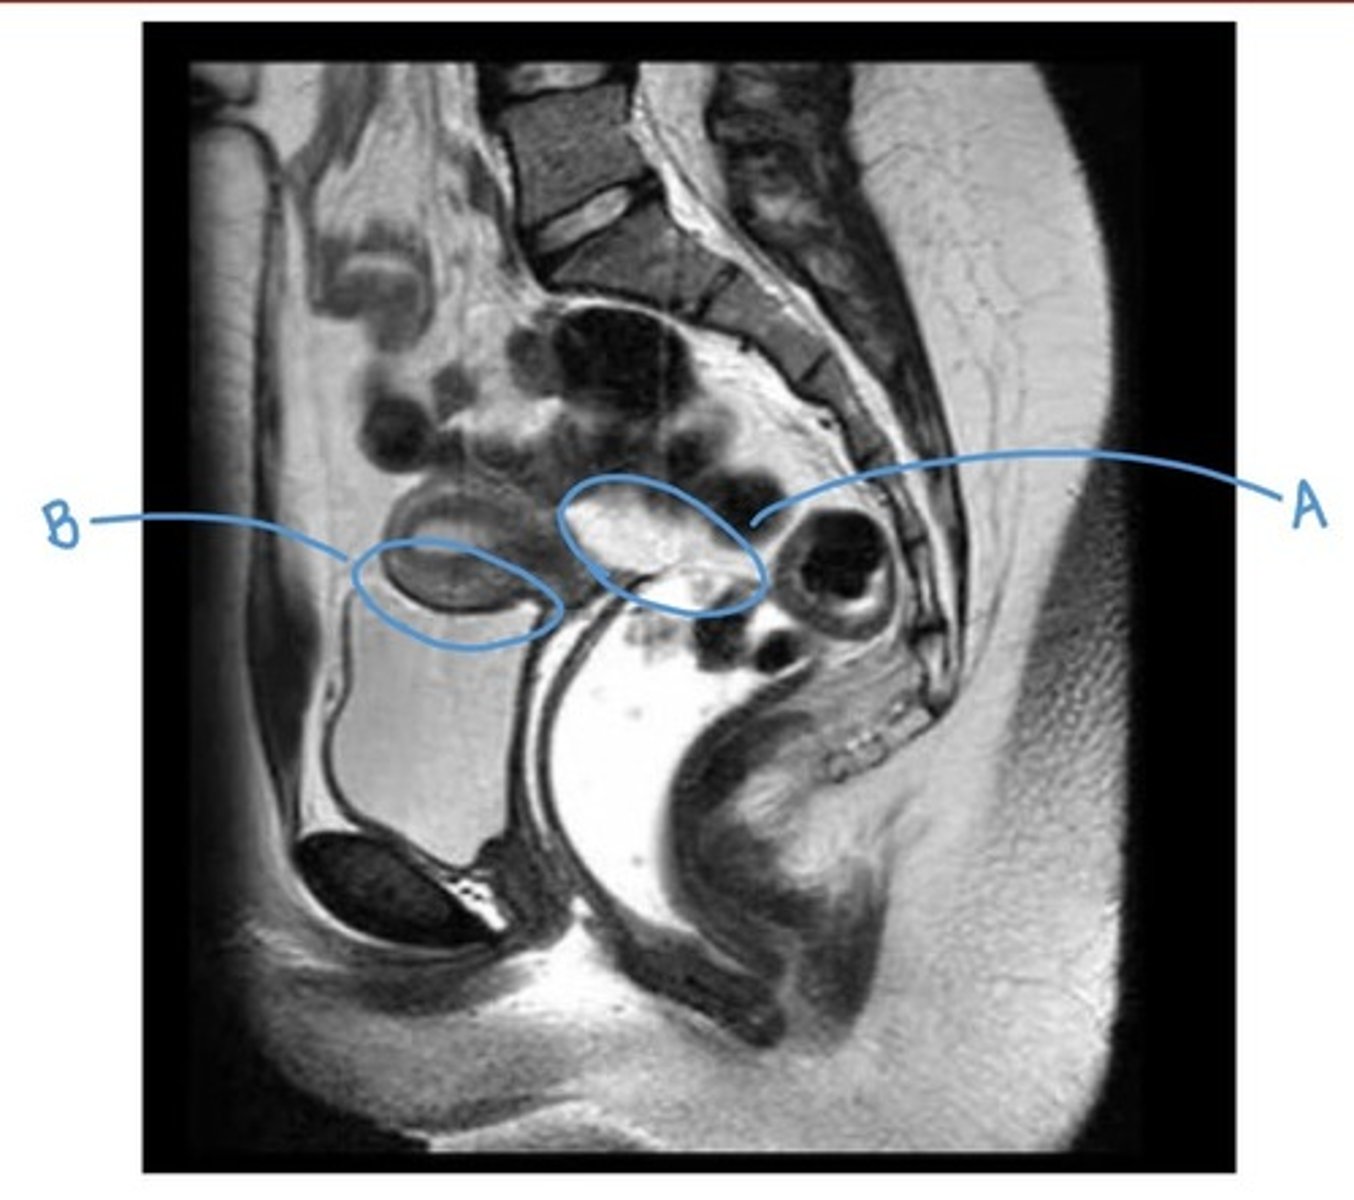

sacral promontory

A

sigmoid colon

B

vagina

C

rectum

D

urethra

E

pubic symphysis

F

retro-pubic space

G

bladder

H

uterus

I